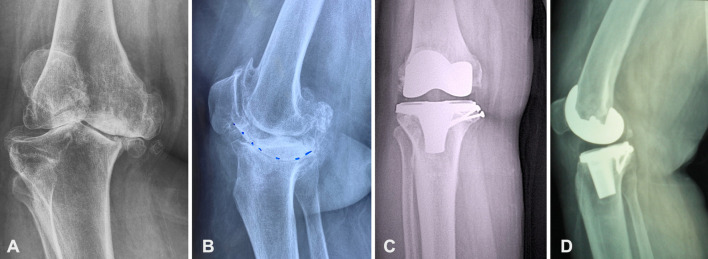

Results: 91 knees in 72 patients at 65.99±8.66 years of age and 8.28±2.58 years follow-up were studied. The tibial defects were managed with extra tibial cuts and adjustment of tibial component position in all, and the addition of structural autograft in 14 knees. 89 (98%) knees survived with a knee society score (KSS) of 79.4±17.6 and were significantly functioning well (P<0.001). Two knees required revision surgery. Significant improvement in outcome measurements was seen in all cases (P<0.001). No radiographic loosening, alignment change, or clinical instability was detected. The tibial plateau reconstruction without bone grafting and the ones that had autologous bone grafting had similar functional results and radiographic outcomes.

Conclusion: TKA with tibial defects of 15-25 mm treated with a semi-constrained posterior-cruciate ligament (PCL) sacrificing condylar prosthesis without any metal wedges or stem extensions with or without additional autogenous bone graft obtained very good functional and radiographic outcome and 97% survival in 6-17 years follow-up.